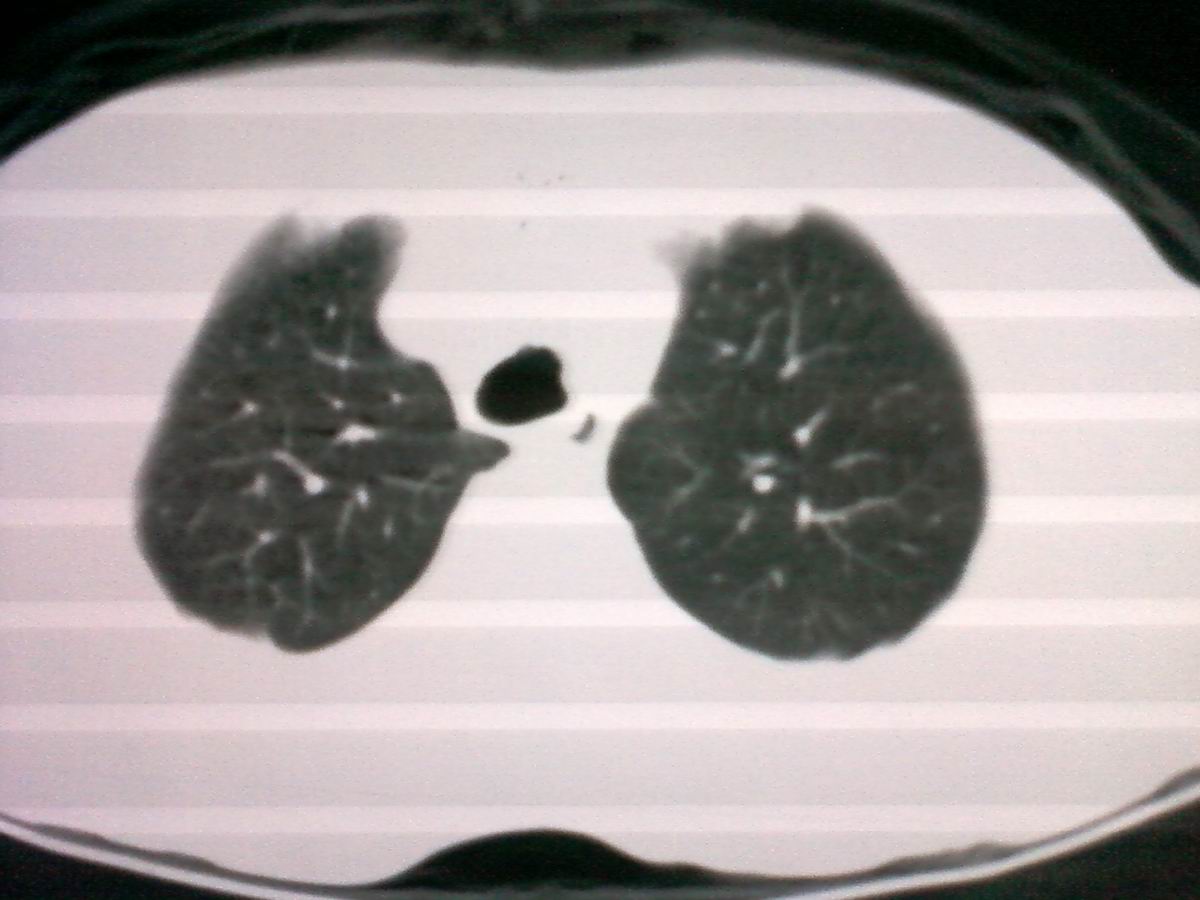

气管后部见半圆形软组织密度病灶,考虑占位,建议气管镜除外鳞癌。

气管上段的肿瘤多为良性乳头状瘤,气管下段的肿瘤多为鳞癌,气管中段的良恶性各占一半。本例位于气管下段,先按恶性处理。不过纤支镜是免不了的。

先咳一下,看看是否痰栓再考虑占位。

气管有占位鳞癌、腺样囊性癌、类癌、粘液表皮样癌。